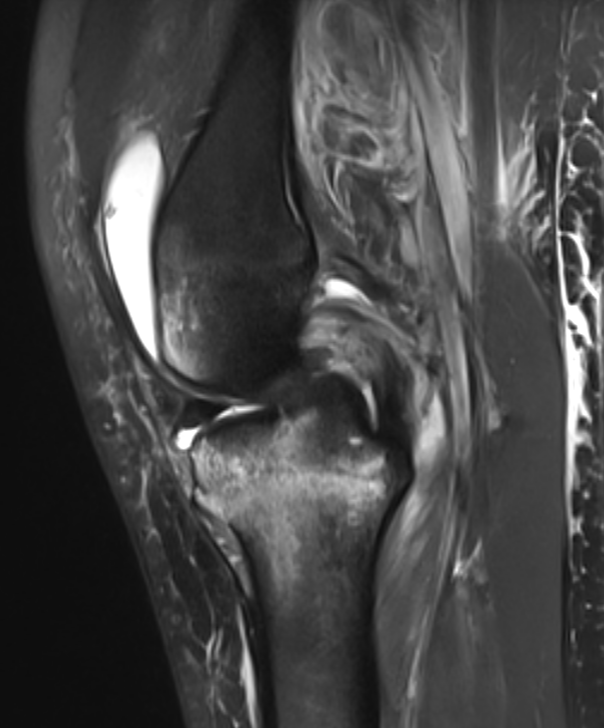

3. PCL injury from hyperextension